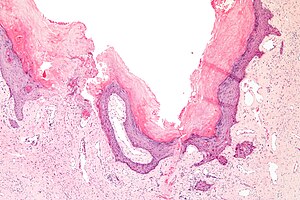

| LM | ectatic superficial dermal vessels with overlying hyperkeratosis (thick stratum corneum); should have "epidermal collarette" (vascular space is surrounded by epidermis on three sides) |

- Ectatic superficial dermal vessels.

- Overlying hyperkeratosis (thick stratum corneum).

- Should have "epidermal collarette".[2]

- Vascular space surrounded by epidermis on three sides.

- Irregular acanthosis.

- Longer rete ridges.